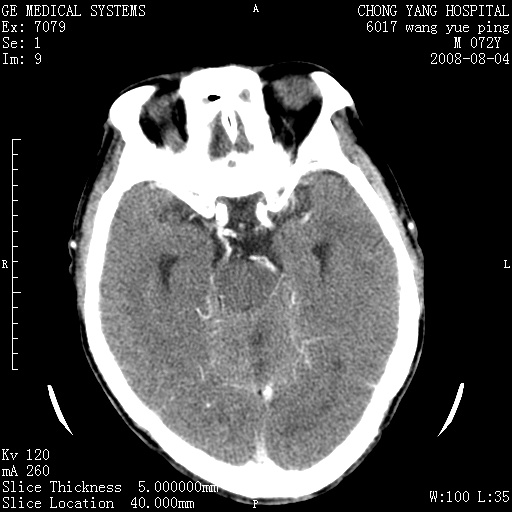

标题: CT14987:M72Y,头痛头昏,BP220/110. [打印本页]

1)考虑左侧小脑脑梗塞。2)脑白质病。3)脑萎缩。4)双侧鼻腔新生物(息肉?)并阻塞性副鼻窦炎。

1.左侧小脑大面积梗塞;2.左侧基底节区腔梗;3.白质疏松;4.脑萎缩;5.慢性副鼻窦炎

1)考虑左侧小脑脑梗塞,建议治疗后复查除外其他,左基底节区腔隙性脑梗塞2)脑白质变性3)脑萎缩。4)双侧鼻腔新生物(息肉?)并阻塞性副鼻窦炎。